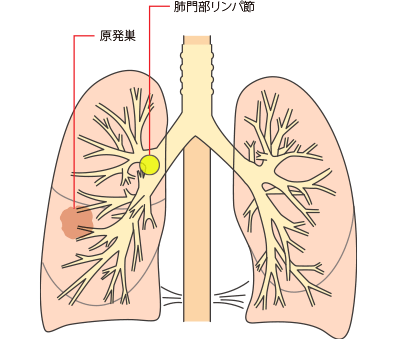

その他、肺がんはがんの発生部位によって肺門型肺がんと肺野型肺がんに分けられます。

| 肺門型肺がん |

| 肺野型肺がん |

肺門型肺がんと肺野型肺がん

同側の気管支周囲かつ/または同側肺門、肺内リンパ節への転移で原発腫瘍の直接浸潤を含める

N1は、最初にできたがん(原発巣)と同じ側の気管支周囲や肺門または肺内リンパ節に転移があることです。